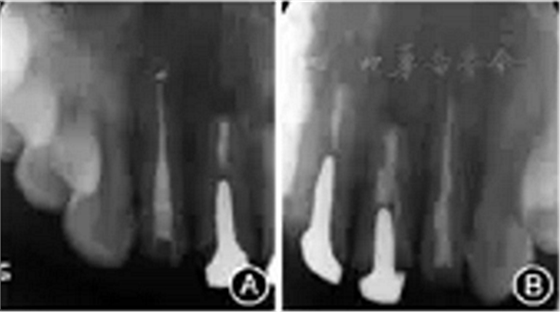

图6 患者显微根尖手术再治疗过程 A:龈缘下方扇形水平切口,翻开组织瓣;B:根尖切除后;C:使用三氧化矿物凝聚体根尖倒充填后检查;D:手术切口缝合术后根尖X线片显示根充糊剂少量超填,根充恰填,倒充填根尖3 mm致密,与桩核末端之间尚有部分空隙(图7)。

图7 患者再治疗完成后即刻根尖X线片 A:糊剂少量超填,根尖3 mm倒充填致密;B:恰填,根尖3 mm倒充填致密。